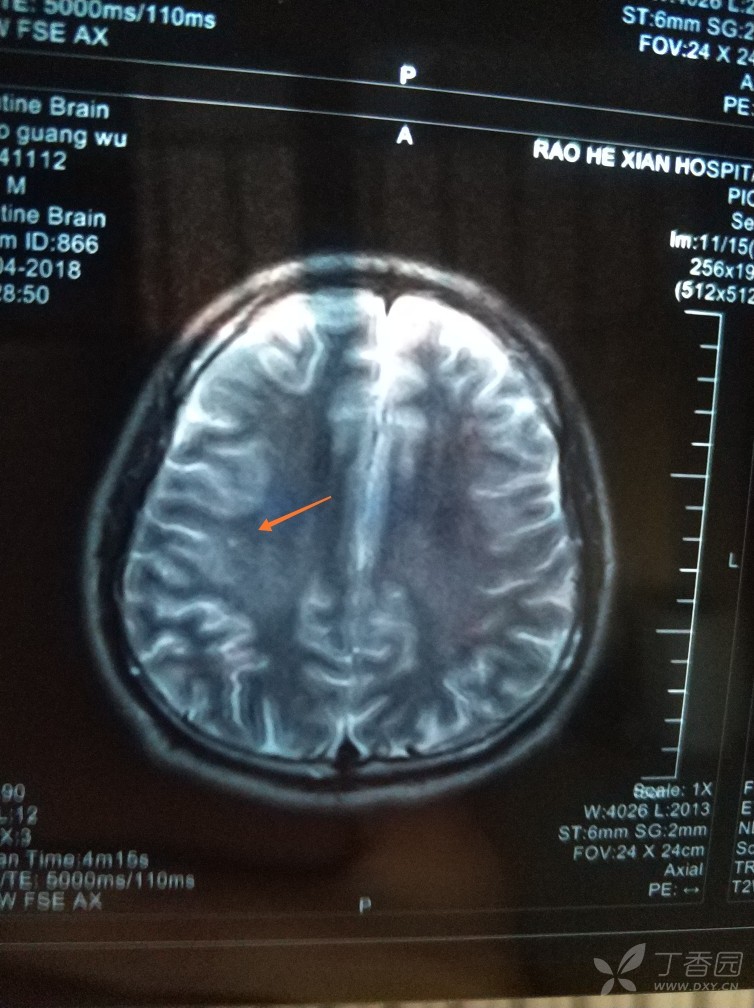

24岁男性,体检发现脑部2处缺血灶 [病例帖]

脑电图存在局灶性放电,头颅磁共振提示「左侧半卵圆区缺血灶」,难道

阅片是有双侧大脑缺血灶,仔细看双侧小脑半球脑沟增多